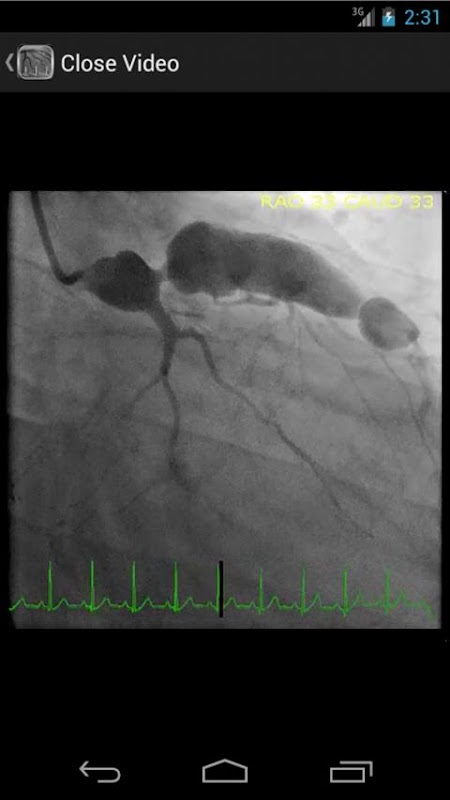

* Kardiyak kateterizasyon laboratuarında yaygın ve nadir görülen bulguların hem fazla 30 videolar (koroner anjiyografi venthkülografi ve aortogramda) içeren aranabilir veritabanı

* Hemodinamik formüller, tablolar ve şekiller dahil olmak üzere 65 den fazla görüntü aranabilir veri tabanı

CathSource eğitim images / videoları yanı sıra ilgili tıp literatüründe değerlendirmeleri içeren, önemli kalp kateterizasyonu ve anjiyografi konularda ayrıntılı bir bakış sağlar. CathSource anlayış ve kateterizasyon laboratuarında kardiyovasküler patoloji tanıyarak size yardımcı olmak için ideal bir uygulamadır.